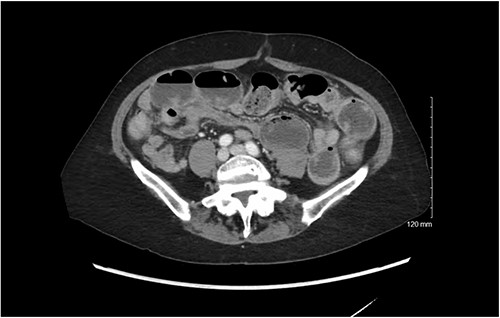

She was well nourished and did not appear to be in significant pain or distress. Her abdomen was soft, mildly distended with tympany, and was diffusely tender without rebound or guarding. She was hemodynamically normal. Significant laboratory values included a white blood cell count of 19 K/mcL, hemoglobin 14 g/dL, liver and renal function was within normal limits, potassium was 3.1 mmol/L, and lactate 2.0. She incidentally was found to have a urinary tract infection (UTI) on urinalysis. A CT scan with IV contrast demonstrated multiple dilated loops of small bowel with air fluid levels and a transition point in the left lower abdomen. There was no evidence of fecalization of the small bowel (Fig. 1). Given her hemodynamic stability and reassuring abdominal exam, the patient was admitted for nonoperative management of her SBO. She was also started on antibiotics for her UTI and plans were made for a Gastrograffin challenge the following day.

CT scan demonstrating dilated loops of small bowel with air fluid levels with distal decompressed loops.